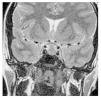

Casos en imagen 4

Case 4

Figuras (3)